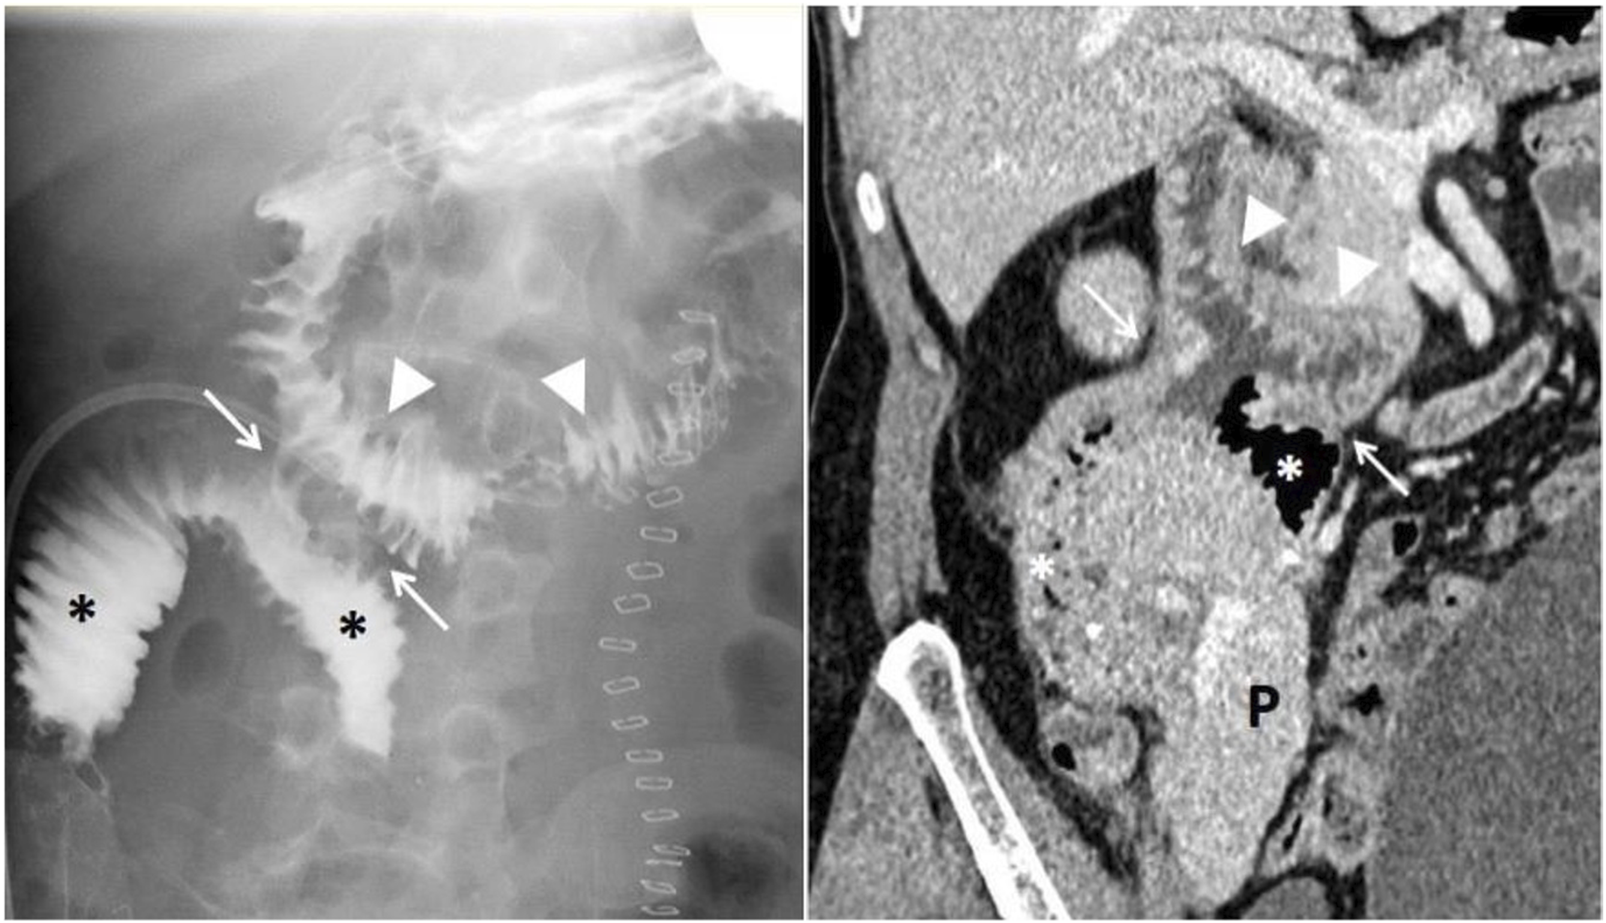

FIGURE 1

Pancreas transplantation with retrocolic graft placement and duodenoduodenostomy for exocrine drainage. Esophagogastroduodenal transit study with Gastrografin (right) demonstrates proper contrast passage through the recipient’s duodenum (arrowheads), the side-to-side duodenoduodenal anastomosis (white arrows), and the graft’s duodenal segment (asterisks), with no evidence of leakage. Abdominal contrast-enhanced computed tomography of the same patient (left) shows a normoenhancing pancreatic graft (P), without collections or other complications.